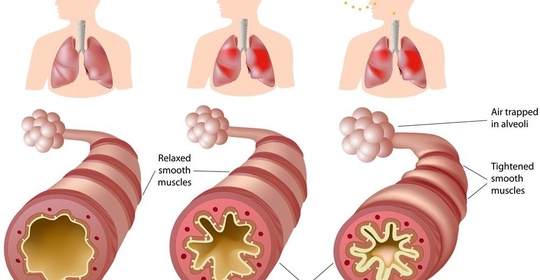

嬰兒腳氣:關注嬰幼兒支氣管炎並發症